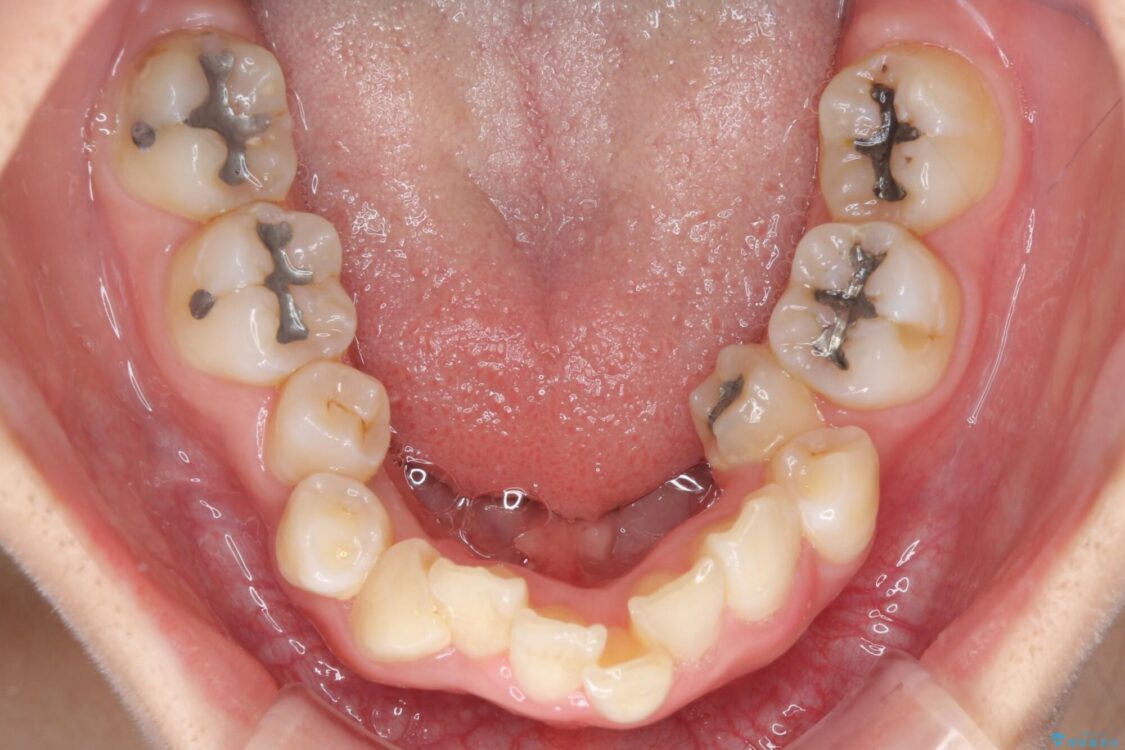

治療前

• デコボコと深い咬み合わせ ワイヤー装置での抜歯矯正 治療前画像

内側に倒れ込んだ歯や下の前歯が隠れてしまうほどの咬み合わせを改善したいとのことで来院された患者様です。

下顎の叢生を解消するために抜歯が必要であり、奥歯の咬み合わせや口元の印象から、上顎も同様に抜歯と判断し、上下左右の第1小臼歯4本抜歯してワイヤー装置にて矯正治療を行うこととしました。